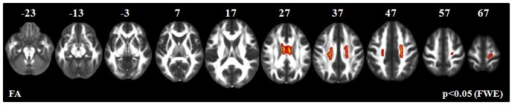

Areas of decreased fractional anisotropy (FA, red-yellow) in PLS individuals v. healthy controls